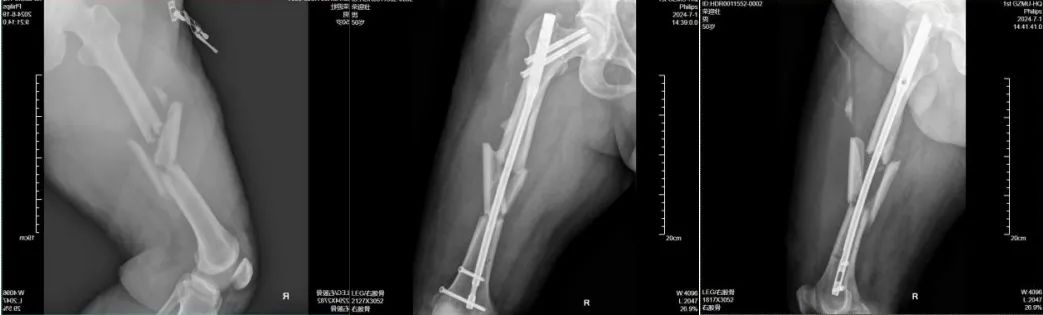

47岁的刘女士(化名),今年在工作时右臂意外遭到重击受伤,拍片发现右肱骨、桡骨远端骨折,严重影响工作和生活,来到广医一院横琴医院就诊。 在广医一院横琴医院骨科副主任医师闫伦春门诊就诊发现其右肱骨骨折、右桡骨远端骨折,闫伦春副主任医师团队为其行“右肱骨骨折闭合复位髓内钉内固定术+右桡骨远端骨折切开复位钢板螺钉内固定术”。术后进行逐步开始功能锻炼,现已完全康复。 02 股骨骨折 股骨是人体最长的骨骼,支撑着整个身体的重量。股骨骨折多见于老年人,常因跌倒等意外发生,严重时可危及生命。 50多岁的公司职员王先生(化名),车祸致右大腿疼痛,活动受限,无法站立、行走,检查发现其右侧股骨颈、股骨干粉碎性骨折,闫伦春副主任医师骨科手术团队为其行“右股骨骨折闭合复位髓内针内固定术,良好的复位和稳定的固定,早期的功能锻炼,伤后3个月后,王先生康复非常满意,没有遗留功能障碍。 03 胫骨骨折 胫腓骨骨干骨折在全身骨折中最为常见,常因车祸、外伤等意外发生,严重时可导致功能障碍甚至截肢的灾难后遗症。 35岁游先生意外致左小腿疼痛,活动受限,不能站立、行走,求治住院,检查发现胫骨骨折,沟通后给予“闭合复位胫骨髓内钉内定治疗”,手术顺利,术后第二天患者下地行走,顺利康复。 治疗亮点 广医一院横琴医院骨科团队日常工作的部分病例展示,在该类骨科损伤的治疗方面积累了大量临床案例和丰富经验,这些手术的亮点是: ➤ 精准复位:采用微创技术,减少手术创伤,确保骨折端精确复位; ➤ 坚强固定:骨折复位的同时,对骨折端进行可靠的固定; ➤ 早期康复:康复科帮助患者早期进行功能锻炼,加速康复进程。 随着医学进步,骨科手术治疗能帮助患者更快更好地恢复运动功能,也能让创口更加美观,那么,骨折发生后应该注意哪些问题。 骨折后如何应急处理? 当发生骨折时,正确的应急处理至关重要。以下是几个关键步骤: ➤ 保持冷静,立即停止活动:避免骨折部位进一步损伤。 ➤ 固定骨折部位:使用身边的物品对骨折部位进行临时固定,减少移动和疼痛。 ➤ 冷敷缓解疼痛:用冰块或冷湿毛巾冷敷,减轻肿胀和疼痛。 ➤ 及时就医:尽快就医,由专业医生进行评估和治疗。 骨折可以保守治疗吗? 骨折是否需要手术取决于骨折的类型、移位程度以及患者的身体状况。一般来说,闭合性骨折且移位不明显时,可以通过保守治疗(如石膏固定)促进愈合;而开放性骨折、粉碎性骨折或移位明显的骨折,则可能需要手术治疗以达到解剖复位和稳定固定。 骨折多久能愈合? 骨折的愈合时间因个体差异而异,一般成人骨折需要3个月到半年左右的时间。但具体时间还取决于骨折的部位、类型、治疗方法以及患者的年龄、营养状况等因素。在愈合过程中,患者应遵循医生的建议进行康复训练,以促进骨折部位的功能恢复。